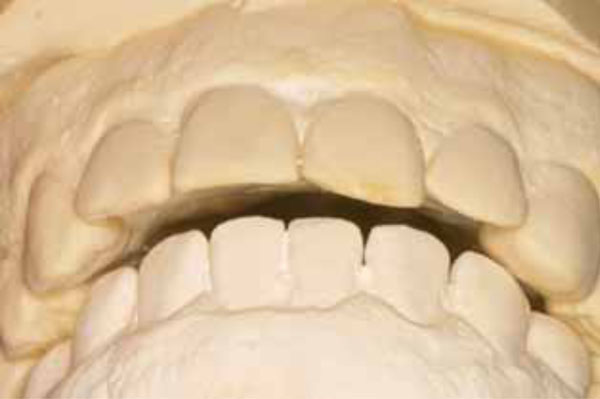

View after composite restorations but before orthodontic repositioning. The teeth were still rotated in toward the tongue at the midline as a result of the fall.

Upper arch after orthodontia.

The goal of orthodontic treatment was to return her teeth to their original pre-trauma positions. No effort was made to correct her Class II malocclusion, which was recognized and discussed but deemed unimportant by the patient. She had always been Class II, she was used to it, and it had not been a problem for her. Therefore, she did not wish to undertake any correction of that condition, and we were able to accommodate her preference in good faith. NiTi round wire (.012-inch) followed by NiTi heat-activated wire (.018 × .025-inch) in fixed metal (.022-inch) brackets was used to reposition the incisors (Figs. 11 and 12). The arch form was restored to a close approximation of the form that it had enjoyed prior to the incident. This correction enabled the patient to resume normal function by eliminating the protrusive interference and the lip biting problem. Examination of post treatment study casts shows overjet restored to original condition (Fig. 13). The comfort and restoration of normal function finally enabled the patient to smile again (Fig. 14).